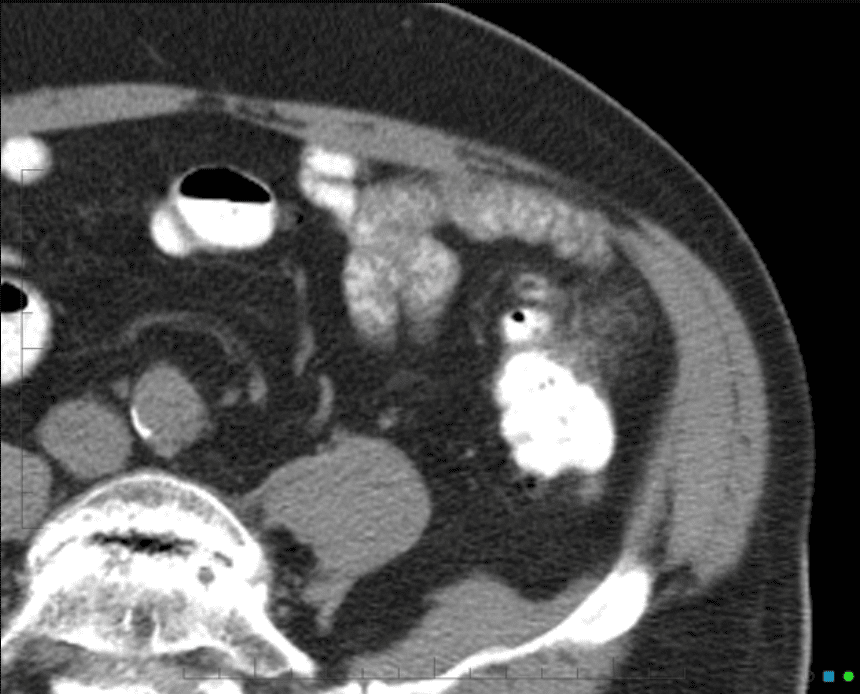

Viêm túi thừa

Viêm túi thừa - Ảnh 3

» Thông tin: Nam giới – 25 tuổi.

» Lâm sàng: Đau hố chậu trái.